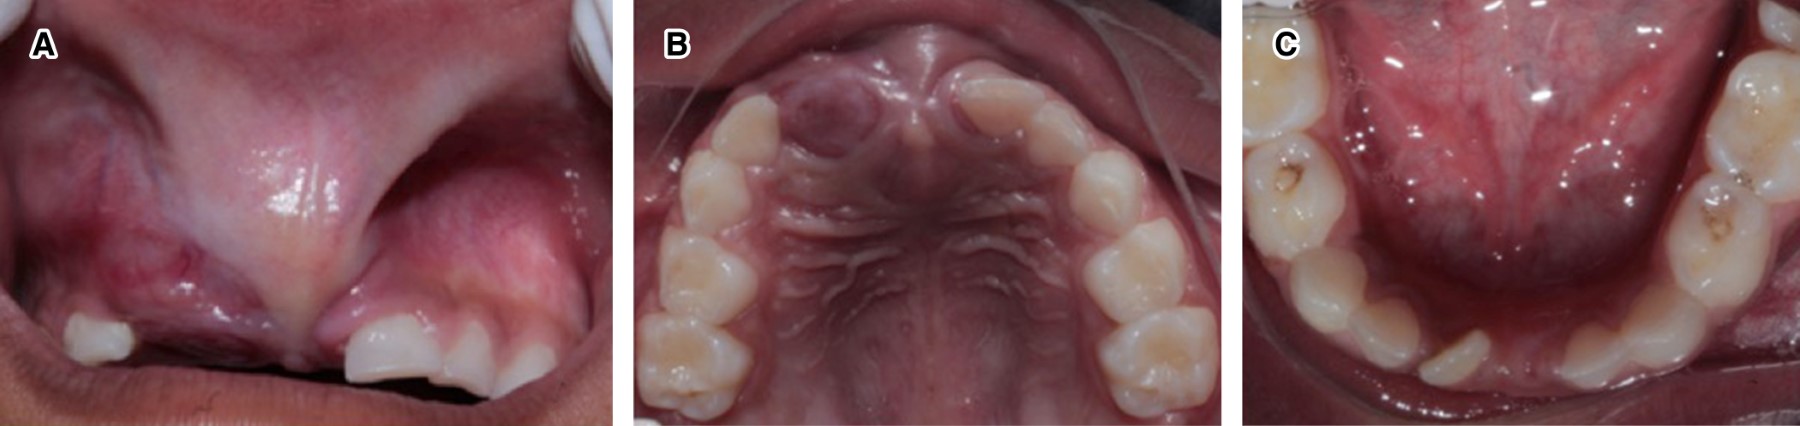

En el examen facial (Figura 1) se notó una clara asimetría y deformación moderada asociada al labio superior. Al examen intraoral, la mucosa labial superior mostró aumento de volumen por encima del frenillo labial, extendido hacia el canino superior derecho (Figura 2A) que involucra al reborde alveolar; se observó de igual manera en el paladar duro anterior, con un aspecto sésil y rojizo, con dolor a la palpación. Dentalmente, se encontraba la paciente en dentición mixta, la ausencia del OD 51 era por una extracción previa, el OD 61 mostraba desplazamiento distal (Figura 2B). Los OD 71 y 81 se habían exfoliado fisiológicamente y el OD 41 se encontraba en erupción temprana. En arcada inferior se observaron los órganos dentarios 72, 73, 74, 75, 41, 82, 83, 84 y 85, los molares deciduos inferiores presentaron lesiones por caries en esmalte y dentina, no hubo alteración en tejidos blandos en dicha arcada (Figura 2C); y en la arcada superior estuvieron presentes los OD 52, 53, 54, 55, 62, 63, 64 y 65.

Figura 2